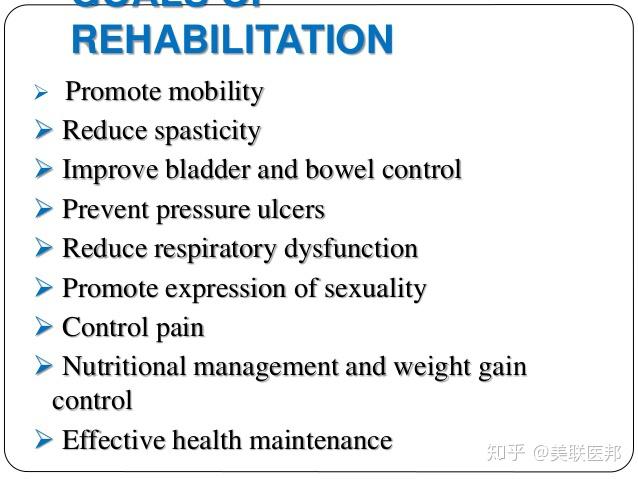

在最初的损伤或病情稳定后,医生将注意力转向预防可能出现的继发性问题,例如去适应、肌肉挛缩、压力性溃疡、大小便问题、呼吸道感染和血栓。

当患者处于康复早期阶段时,康复团队将积极介入患者的治疗。美国的康复医疗团队可能包括物理治疗师、职业治疗师、康复护士、康复心理医生、社会工作者、营养师、娱乐治疗师以及专门从事物理医学(理疗师)或脊髓损伤的医生。

在康复的初始阶段,治疗师通常强调维持和加强现有的肌肉功能,重新训练精细运动技能和学习适应性技术以完成日常任务。

患者将接受有关脊髓损伤的影响以及如何预防并发症的教育,将获得有关重建生活和提高生活质量和独立性的建议。

患者将学到许多新技能,并且将使用可以帮助其尽可能独立生活的设备和技术。医生鼓励患者恢复其最喜欢的爱好,参加社交和健身活动,并返回学校或工作场所。

药物可用于治疗脊髓损伤的一些影响。包括控制疼痛和肌肉痉挛的药物,以及可以改善膀胱控制、肠道控制和性功能的药物。